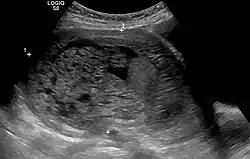

Die Blasenmole (Mola cystica) oder Traubenmole (Mola hydatidosa) ist eine Störung der Embryonalentwicklung in der Schwangerschaft. Durch eine Erweiterung der kleinen Plazentagefäße kommt es zu einer blasenartigen Umwandlung der Plazentazotten mit Einschmelzung des umgebenden Bindegewebes. Der Trophoblast zeigt eine gesteigerte Proliferationsaktivität.

Es wird zwischen teilweiser (90 %) und vollständiger (10 %) Blasenmole unterschieden. Die Übergänge zwischen der destruierenden (invasiven) Blasenmole und dem Chorionepitheliom sind fließend und in der Literatur nicht einheitlich. Begleitend zu einer Blasenmole treten bis kindskopfgroße Luteinzysten des Eierstocks auf, die sich infolge der hohen Sekretion von Gonadotropin (hCG) im Sinne eines Überstimulationssyndroms bilden.[1]

Anzeichen für eine Blasenmole können ein besonders schnell wachsender Uterus (Gebärmutter), ein hoch positiver Schwangerschaftstest, das Fehlen der fetalen Herztöne sowie besonders starke Schwangerschaftsübelkeit sein.

Die Diagnose wird über erhöhte Werte für das humane Choriongonadotropin (β-hCG) sowie über die Darstellung der verdickten Plazenta in Ultraschalluntersuchungen gestellt.